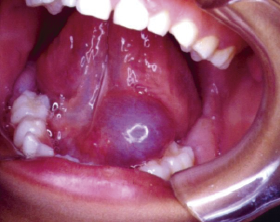

También llamada Medicina Bucal, es la rama de la odontología que se encarga del diagnóstico y manejo de las enfermedades propias de la boca y de las enfermedades sistémicas (de otros sitios del organismo), que tienen manifestaciones bucales.

• El cáncer oral, el diagnóstico y tratamiento quirúrgico de la lesión y la rehabilitación con la somato prótesis. También se encarga del manejo de las implicaciones o consecuencias de la radioterapia y quimioterapia.

El estomatólogo hace parte de un equipo de salud y está en la capacidad de diagnosticar patologías infecciosas, tumorales y de malformación, tomar biopsias y realizar tratamientos de urgencias, de síndromes dolorosos y disfunciones miofaciales y de la articulación temporo mandibular (ATM).